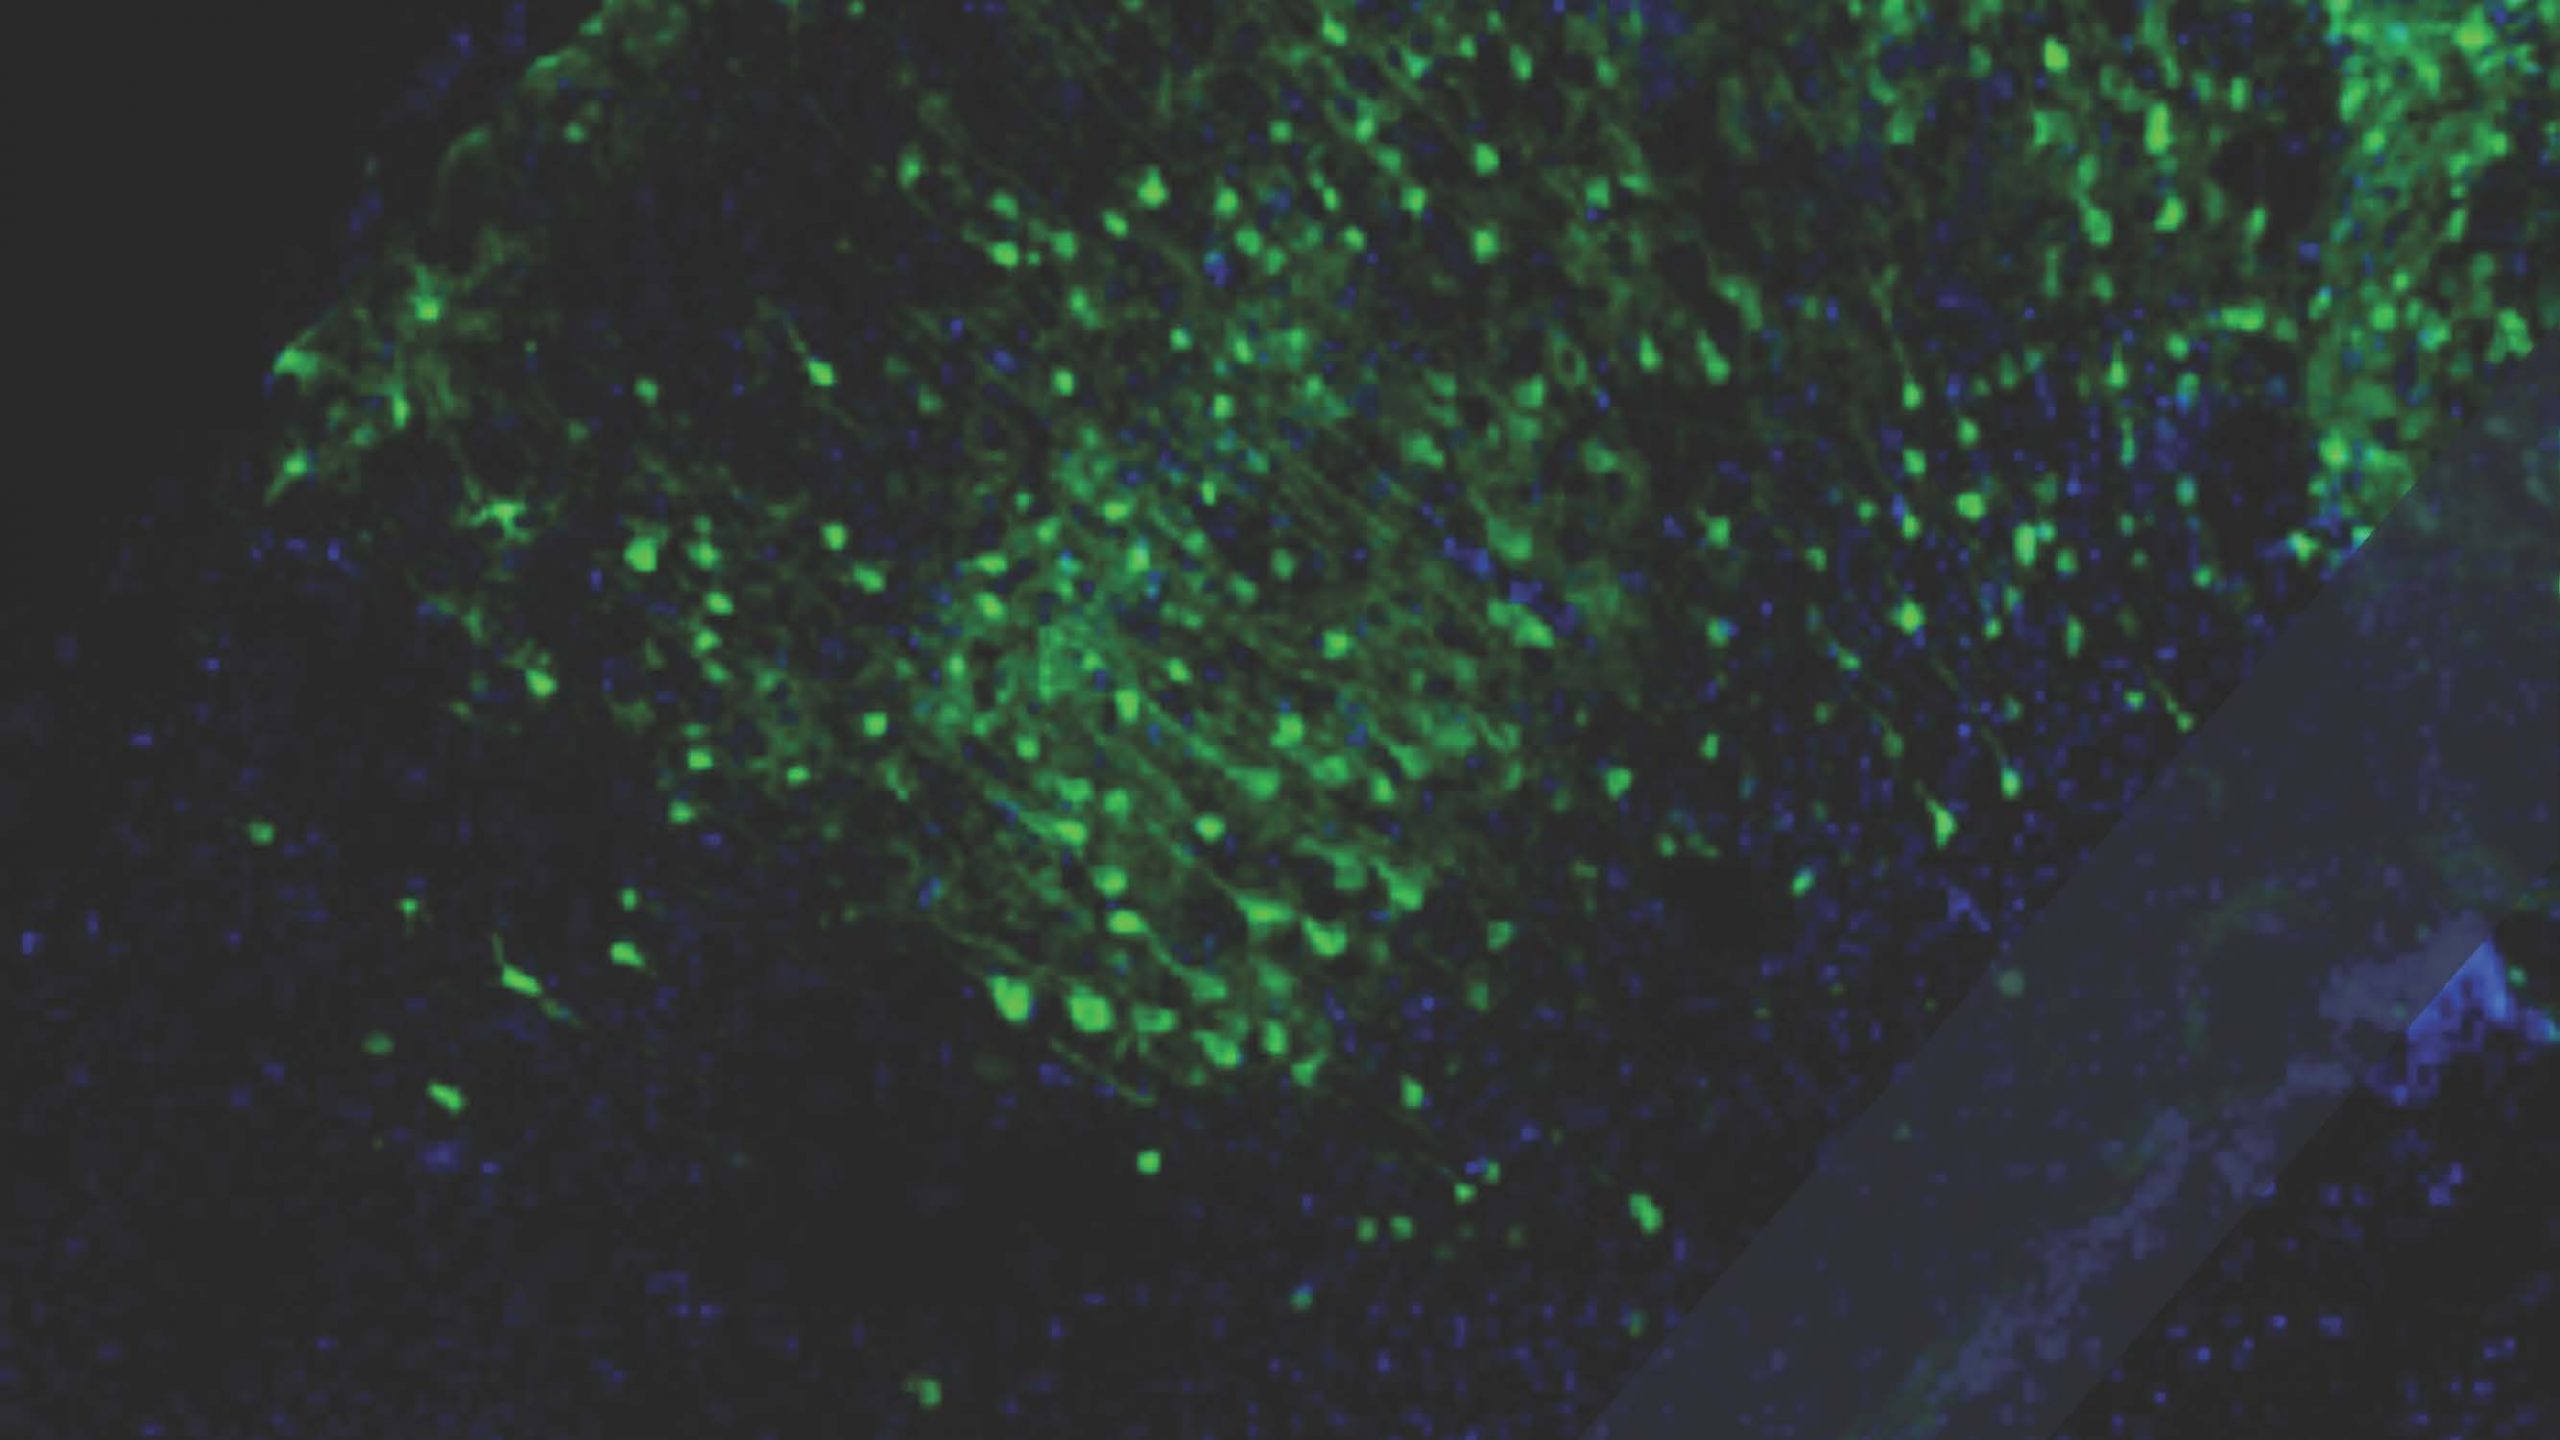

Zooming in on mouse brain development reveals origins of human glial cancers

Mapping the roots of brain cancer